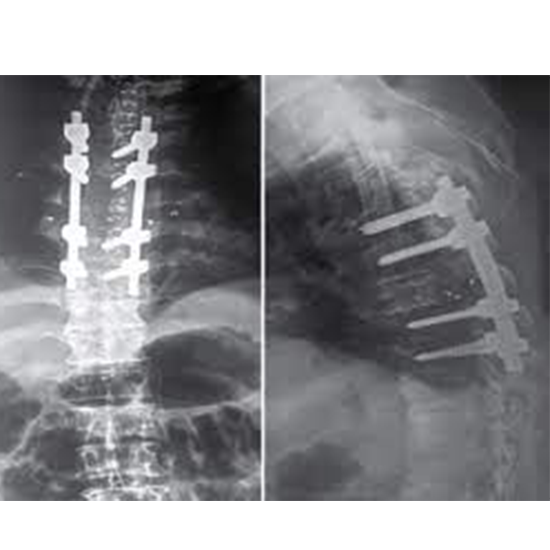

X-rays of the dorsal spine (thoracic spine) visualize the twelve thoracic vertebrae (T1 through T12), which make up the middle of your backbone. Additionally, it is beneficial to visualize their intervertebral discs and the surrounding soft tissues, such as skin and muscles.

The doctor gives this test to determine the source of persistent back pain, look for any injury or fracture to the spinal bones, and identify potential disc disorders such as spondylolisthesis.